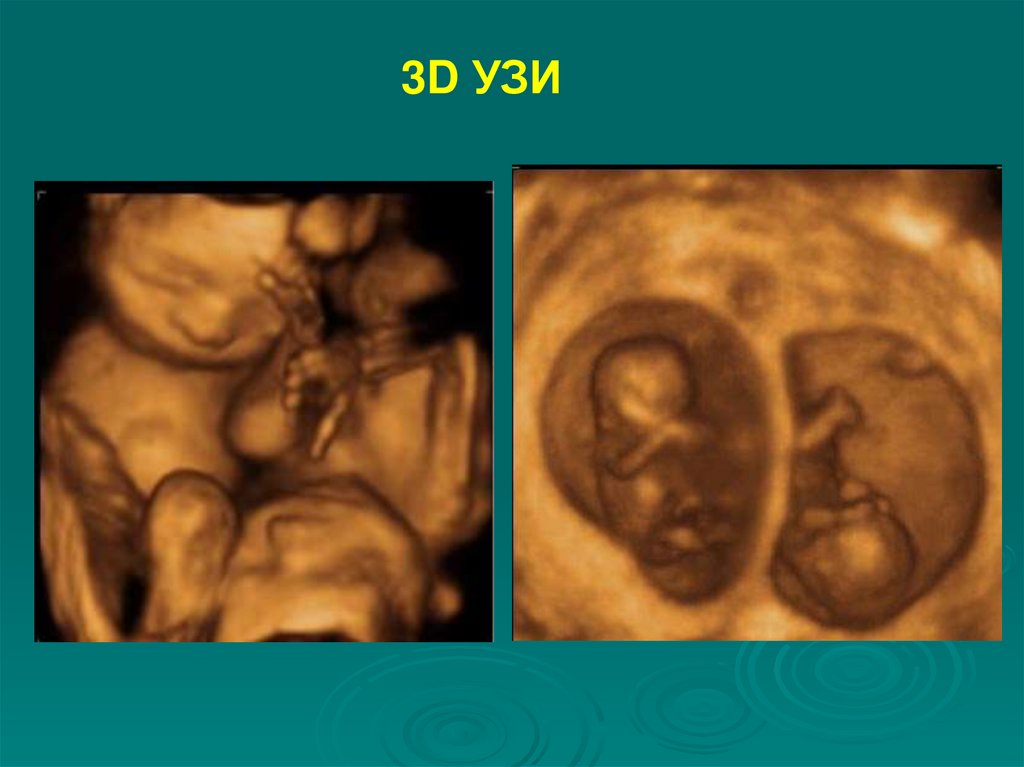

3D УЗИ